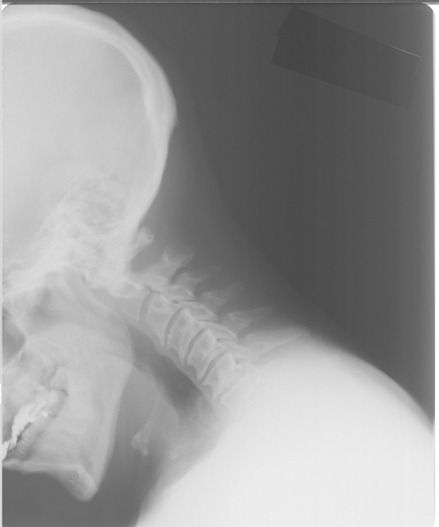

Decapitação interna, ou luxação traumática atlanto-occipital, trauma que ocorre quando há o deslocamento anterior do crânio com relação à coluna vertebral. De acordo com um estudo de 2006, o paciente a experimentar a sensação de que sua cabeça "está caindo".

Uma vez que os tipos de lesão na cabeça podem causar decapitação interna e normalmente também envolver severos danos nervosos ou o corte da espinal medula, o resultado usual é a paralisia ou morte.